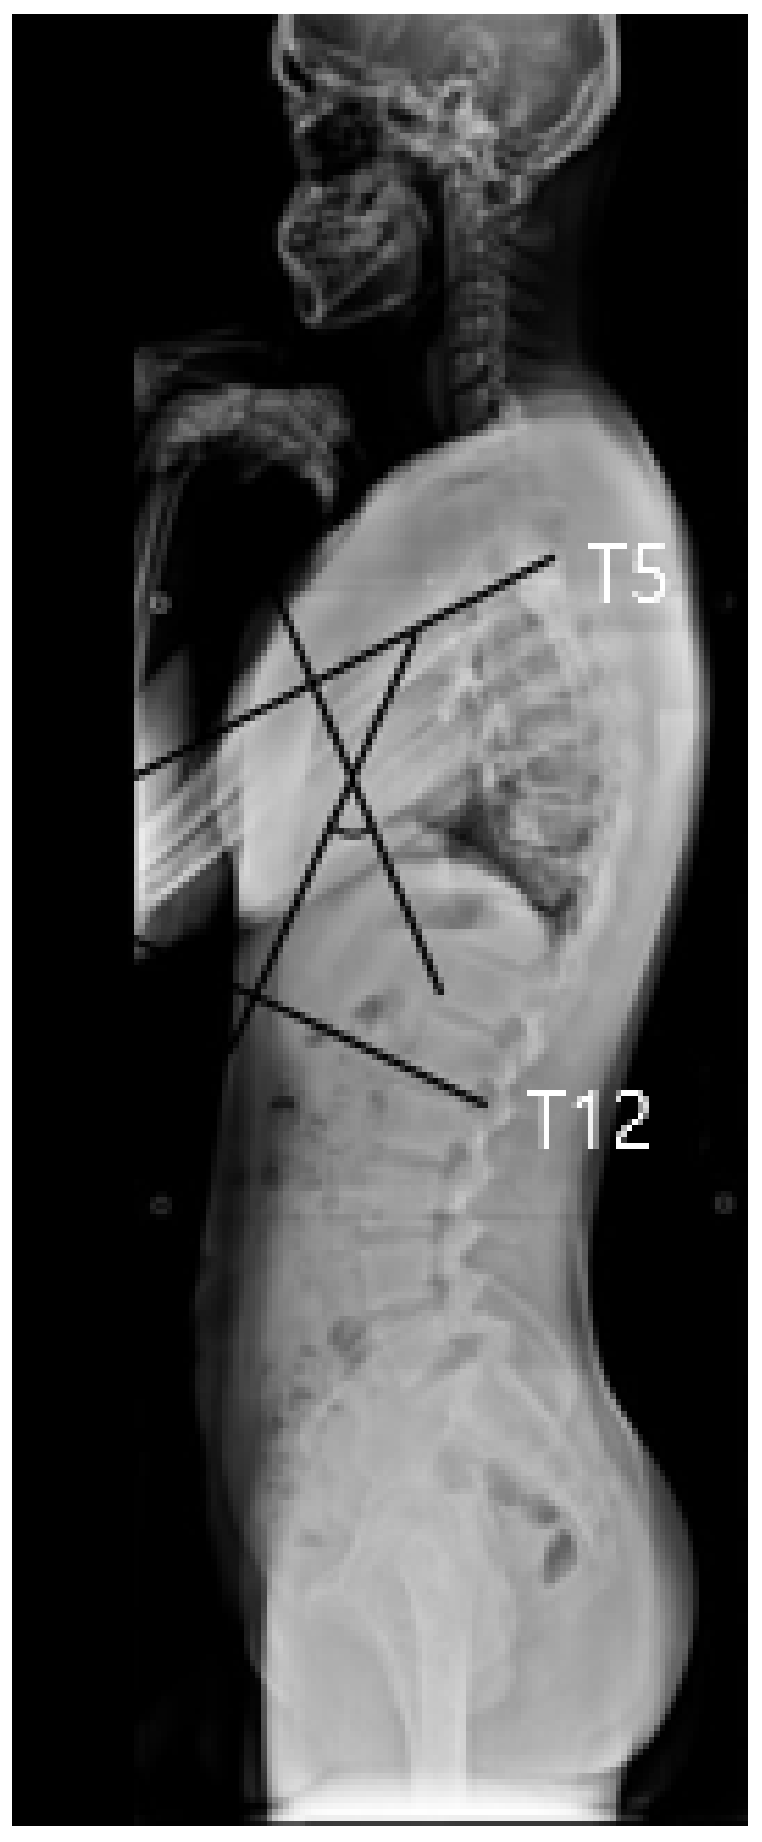

2.3. X-Ray Examination to Measure Cobb’s Angle and Forward Head Angle

| Cobb’s angle (°) | EG | 38.22 ± 3.76 | 26.95 ± 5.03 | 0.000 *** |